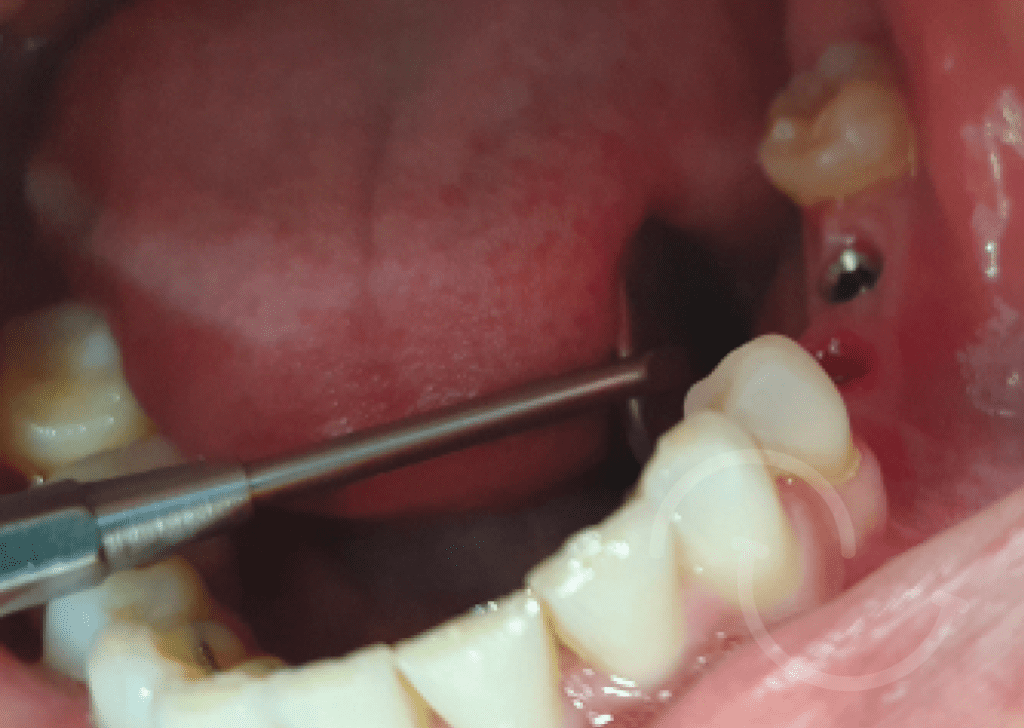

Caso expansion Osea

Casos de regeneración ósea vertical y horizontal con membrana Cytoplast